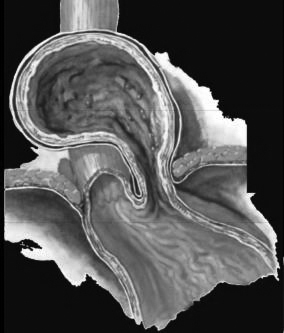

Hernie hiatale type II ( type avec

estomac est enroulement sus diapragmatique .Le

cardia est en place |